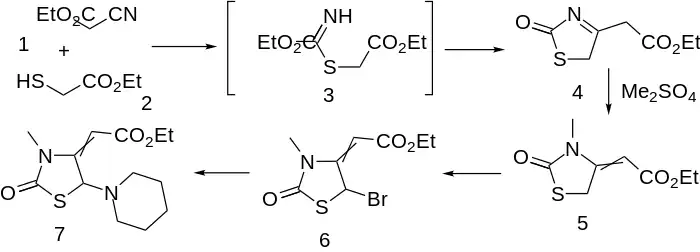

Condensation of ethyl mercaptoacetate with ethyl cyanoacetate leads to thiazolinone (4); an intermediate such as 3, involving addition of the mercaptide to the nitrile function can reasonably be invoked. M/ethylation with di(m)ethyl sulfate proceeds on nitrogen with the concomitant shift of the enamine to afford olefin (5). Bromination of the active methylene (6) followed by displacement of halogen by piperidine affords the choleretic piprozolin (7).